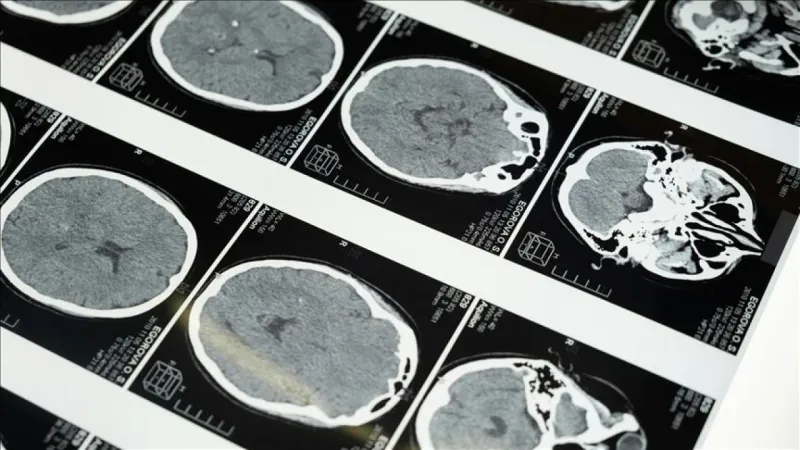

Prof. Dr. Hüseyin Beğenik, bilimsel çalışmalarında obezitenin sadece diyabet ve kalp hastalıkları için değil, mide kanseri açısından da ciddi bir risk faktörü oluşturduğunu belirtiyor. "Yeni bilimsel bulgular, obezitenin bazı kanser türleriyle de yakın ilişkili olduğunu gösteriyor. Özellikle mide kanseri gibi ölümcül hastalıklarla olan bağlantısı, hem bilim insanlarını hem de halk sağlığı uzmanlarını alarma geçirdi," diyor Beğenik.

Bu bulgular, obezitenin vücuttaki kronik inflamasyonu artırması ve hormonal dengesizliklere yol açması gibi mekanizmalarla kanser gelişimini tetikleyebileceğini gösteriyor. Obez bireylerde, insülin direnci ve yüksek insülin seviyeleri, kanser hücrelerinin büyümesini ve yayılmasını kolaylaştırabilir. Ayrıca, yağ dokusunun salgıladığı bazı hormonlar ve sitokinler de kanser riskini artırabilir.